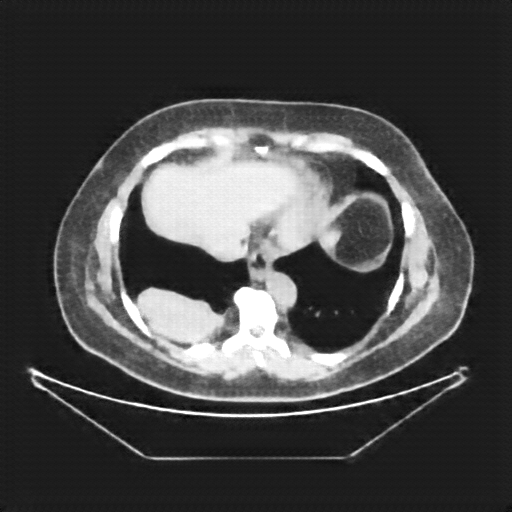

Original NATIVE CT scan (input)

Full window (WL 1023.5, WW 4095 β†’ Low βˆ’1024, High +3071)

Actual HU range: [-160.0, 240.0]